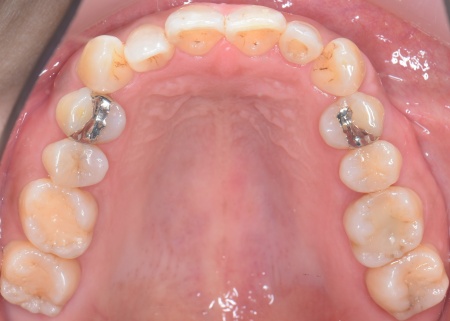

矯正方法としては、上下の歯全体の表面にブラケットと呼ばれるボタン状の装置を接着し、そこにワイヤーを通して歯を動かすマルチブラケット装置を採用しました。

とくに上の左右奥歯には、矯正用ミニインプラント(矯正治療専用の小さなネジ)を埋入し、奥歯を歯茎の方向に押し下げる「圧下」という治療を行っています。これにより開咬が解消され、前歯でしっかり噛めるようになりました。

最後に、右下奥歯に装着されていた銀の詰め物を外し、強度と審美性に優れた白い被せ物であるジルコニアセラミッククラウンを装着します。見た目や噛み合わせ、使用感などに問題がないことを確認し、治療を終了しました。